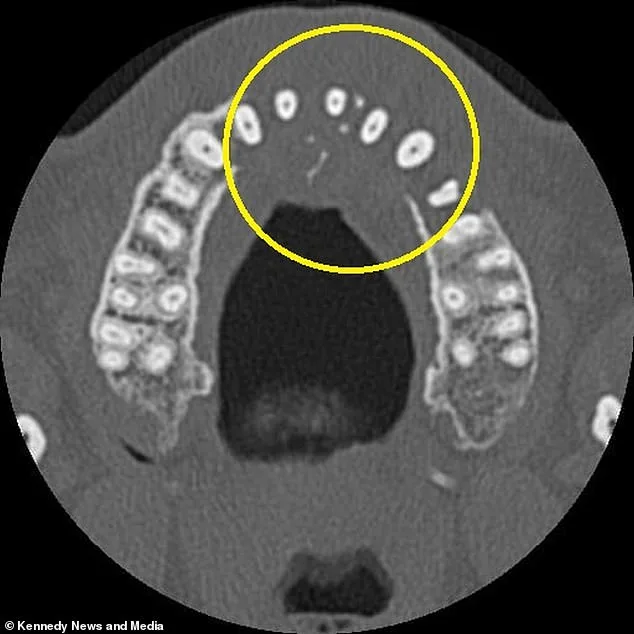

A routine X-ray at the local dentist in Portugal revealed a shocking absence of bone on the left side of his upper jaw. Further imaging with a CT scan uncovered a mass growing in his sinus cavity, which had spread under his nose. Upon returning to the UK, additional tests confirmed a stage two diagnosis of diffuse large B-cell lymphoma (DLBCL), a fast-growing form of non-Hodgkin lymphoma that affects white blood cells. The tumor had 'eaten' through his upper jawbone, and the cancer had already begun to spread to his neck.

Vieira's experience underscores the potential risks of ignoring seemingly minor symptoms. 'If I had ignored the toothache, it could have gotten much worse,' he said. 'I might have lost my teeth, and the cancer could have spread further.' His symptoms, which included a dull ache in his left canine, wobbling teeth, pain when blowing his nose, and the sudden appearance of a small hard lump near his right nostril, were initially disconnected in his mind. Only after the diagnosis did he understand the connection between his dental pain and the aggressive tumor growing in his sinus.